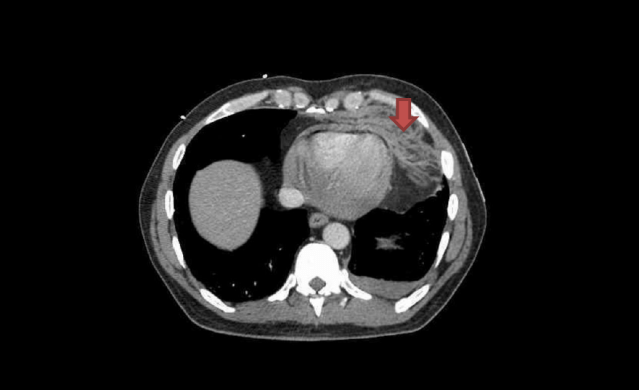

Angioembolisation

Angioembolisation in renal trauma is effective in selected patients.

Trauma CT: Blue arrow is contrast ‘blush’=active bleeding point. Red arrow is perinephric haematoma.

When transferring these patients from smaller hospitals to larger centres, consider whether initial destination should be the ED for rapid re-assessment prior to entering IR suite.